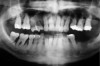

In this example, the more predictable option would have been to place an implant in the No. 30 position and restore the area as three single units. However, the treatment delivered involved a four-unit fixed bridge, which then included tooth No. 28. Unfortunately, this bridge failed at approximately 5 years (Figure 7 and Figure 8) because of a root fracture of tooth No. 29 and advanced furcation involvement with residual endodontic infection of tooth No. 30. The inclusion of tooth No. 28 into the bridge also decreased its long-term prognosis because of its preparation.43 The alternative restorative option of a RPD also would decrease the prognosis of the RPD abutment teeth, which fail more often than FPD abutment teeth.43

Figure 9 shows the implant placement at the time of extraction and Figure 10 shows the implant-supported fixed bridge. In one surgical procedure, the implants in the Nos. 29 and 31 positions were placed at the time of the extraction of these two teeth. The implants were restored approximately 3 months after placement.

Figure 7  Condition of the teeth seen in Figure 6, approximately 5 years after restoration. Note the extensive furcation involvement of tooth No. 31 and its residual periapical radiolucency.

Figure 7

Figure 8  Same case as in Figure 7 showing teeth Nos. 28 and 29. Note that tooth No. 28 was included into the four-unit restoration, and the small radiolucency on the distal tooth No. 29, which was associated with a root fracture.

Figure 8

Figure 9  Extraction of teeth Nos. 29 and 31 with immediate implants (Straumann USA, Waltham, MA) placed into the site.

Figure 9

Figure 10  Implants seen in Figure 9 restored approximately 3 months after placement.

Figure 10